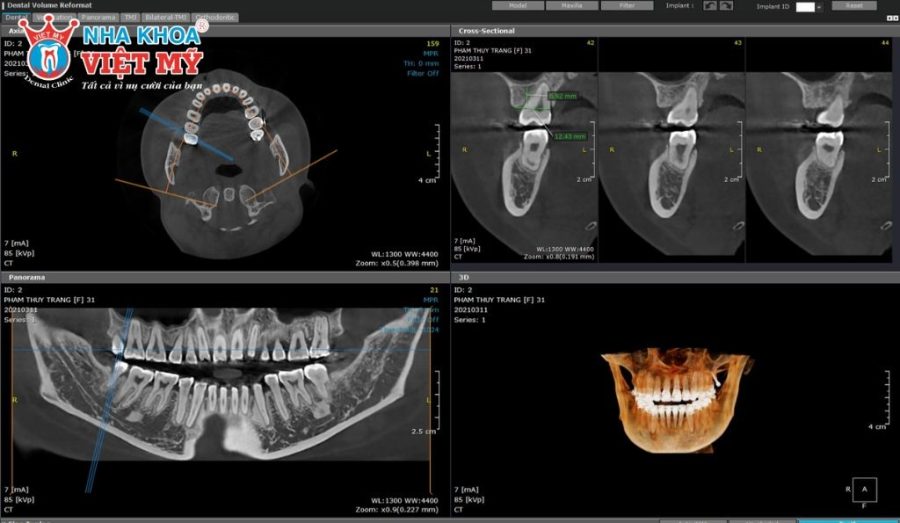

– Chụp CT ConeBeam 3D: Đây là công nghệ quét 3D răng cho hình ảnh chi tiết về cấu trúc xương, mật độ xương và vị trí các dây thần kinh. Nhờ đó, nha sĩ có thể chẩn đoán tình trạng bệnh nhân để đưa ra kết luận cấy ghép Implant hay cần ghép xương/ nâng xoang trước đó.

– Phần mềm mô phỏng Implant 3D: Sử dụng các phần mềm chuyên dụng trên máy tính để tạo mô phỏng chi tiết hình ảnh răng 3 chiều (rộng, sâu, cao). Từ đó, bác sĩ sẽ có cái nhìn tổng quát hơn về tình trạng răng, tạo máng hướng dẫn.